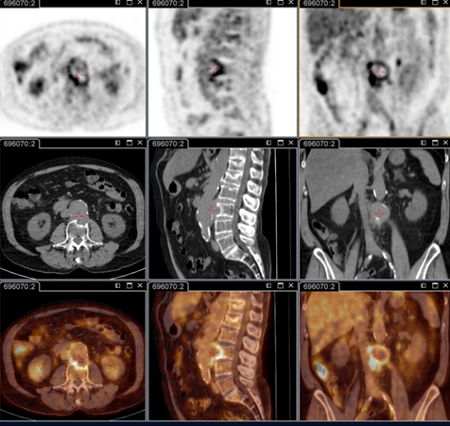

18F-ფთორდეზოქსიგლუკოზით (FDG) PET/CT სკანირება

ტესტი

კრიტიკული მნიშვნელობისაა პერსისტენტული ფოკალური ინფექციების იდენტიფიცირებისათვის.[78]

კვლევის ამ მეთოდით შესაძლებელია ენდოკარდიტის, სისხლძარღვოვანი ინფექციის, ლიმფადენიტის, ძვალსახსროვანი ინფექციების გარჩევა. ამ მიდგომის გარეშე ჩამოთვლილი მდგომარეობების იდენტიფიცირება შეუძლებელია.

ამჟამად აღნიშნული კვლევა სტანდარტული ანატომიური კვლევის მეთოდია პერსისტენტული სიმპტომების და/ან პერსისტენტულად მომატებული სეროლოგიური მაჩვენებლების და/ან სისხლის ან შრატის დადებითი პჯრ-ის მქონე პაციენტებში, ან ნებისმიერ შემთხვევაში როცა კლინიკური გამოვლინება არ შეესაბამება პირველად ინფექციას.[3]

კონკრეტულად რეკომენდებულია შემდეგი პაციენტებისთვის: მწვავე Q ცხელება პერსისტენტული I ფაზის IgG ≥1:800 და/ან ვლინდება ცუდი კლინიკური განვითარება; მწვავე Q ცხელება სისხლძარღვის გრაფტის ან ანევრიზმის ანამნეზით; ან აუხსნელი (I ფაზის IgG ≥1:800) სეროლოგიით ან პერსისტენტულ ინფექციაზე კლინიკური ეჭვის დროს.

ასევე გამოსადეგია ინფექციის იდენტიფიცირება პაციენტებში, რომელთაც აღენიშნებათ სისხლძარღვის პროთეზი და/ან ანევრიზმა. საჭიროა გადაწყვეტილების მიღება, თუ რომელ პაციენტს ესაჭიროება ქირურგია ინფიცირებული სისხლძარღვოვანი ქსოვილების ამოსაკვეთად.[Figure caption and citation for the preceding image starts]: Q ცხელების ენდოკარდიტი, PET სკანირება: 18F-ფთორდეზოქსიგლუკოზა PET/CT. პაციენტი უსიმპტომოა, ანამნეზში აქვს სარქველის პრობლემა, მომატებულია სეროლოგია. PET სკანირებით დიაგნოსტირდა აორტის ენდოკარდიტი ბუნებრივ სარქველზე, თორაკალური და წელის აორტის მიკოზური ანევრიზმებითInstitut Hospitalo-Universitaire Méditerranée Infection (პაციენტის ნებართვა აღებულია) [Citation ends].

[Figure caption and citation for the preceding image starts]: Q ცხელების აორტული მიკოზური თორაკალური ანევრიზმა - PET სკანირება: 18F-ფთორდეზოქსიგლუკოზა PET/CT. პაციენტი უსიმპტომოა, ანამნეზში აქვს სარქველის პრობლემა, მომატებულია სეროლოგია. PET სკანირებით დიაგნოსტირდა აორტის ენდოკარდიტი ბუნებრივ სარქველზე, თორაკალური და წელის აორტის მიკოზური ანევრიზმებითInstitut Hospitalo-Universitaire Méditerranée Infection (პაციენტის ნებართვა აღებულია) [Citation ends].

[Figure caption and citation for the preceding image starts]: Q ცხელების აორტული მიკოზური ანევრიზმა - PET სკანირება: 18F-ფთორდეზოქსიგლუკოზა PET/CT. პაციენტი უსიმპტომოა, ანამნეზში აქვს სარქველის პრობლემა, მომატებულია სეროლოგია. PET სკანირებით დიაგნოსტირდა აორტის ენდოკარდიტი ბუნებრივ სარქველზე, თორაკალური და წელის აორტის მიკოზური ანევრიზმებითInstitut Hospitalo-Universitaire Méditerranée Infection (პაციენტის ნებართვა აღებულია) [Citation ends].